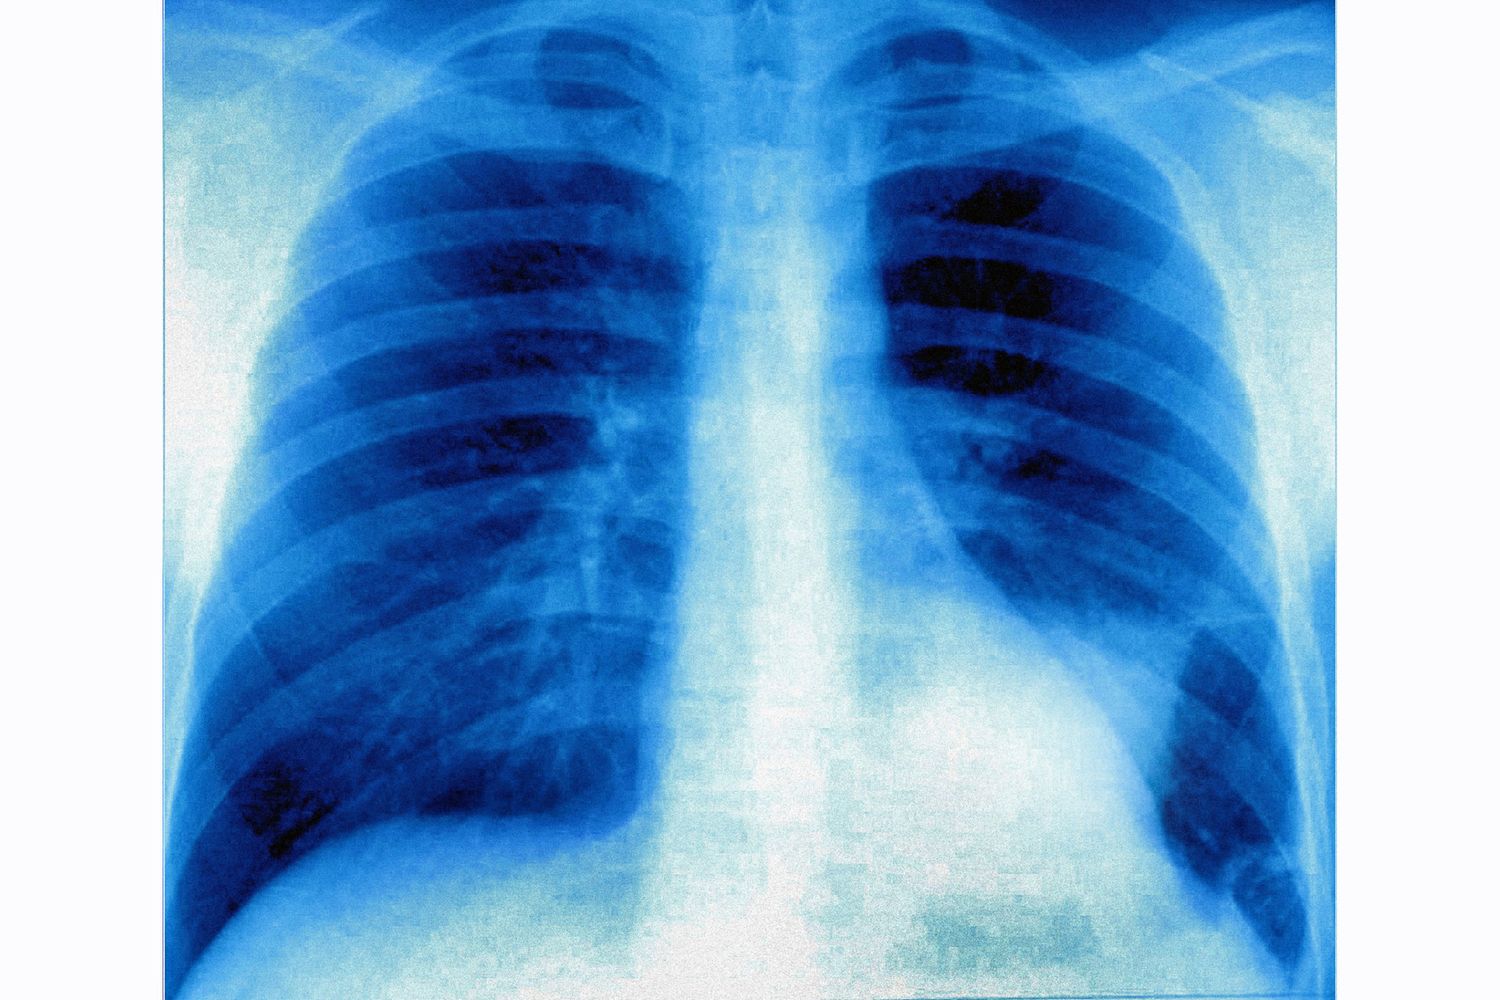

AGI - Uno studio su un nuovo farmaco ha dimostrato la possibilità di diminuire la crescita tumorale in studi preclinici condotti in laboratorio sul modello murino con tumore al polmone del sottotipo molecolare K-RAS mutato. La ricerca è frutto di un lavoro internazionale guidato da Elena Levantini dell'Istituto di tecnologie biomediche del Consiglio nazionale delle ricerche (Cnr-Itb) di Pisa dove coordina il Laboratorio di oncologia molecolare, e con incarichi da ricercatrice anche nel reparto di Ematologia/Oncologia dell'ospedale BIDMC della Harvard Medical School di Boston. Il tumore del polmone è la prima causa di morte per cancro, responsabile di circa un terzo delle morti per malattie oncologiche. Nonostante gli enormi progressi scientifici, al momento le opzioni terapeutiche sono ancora limitate.